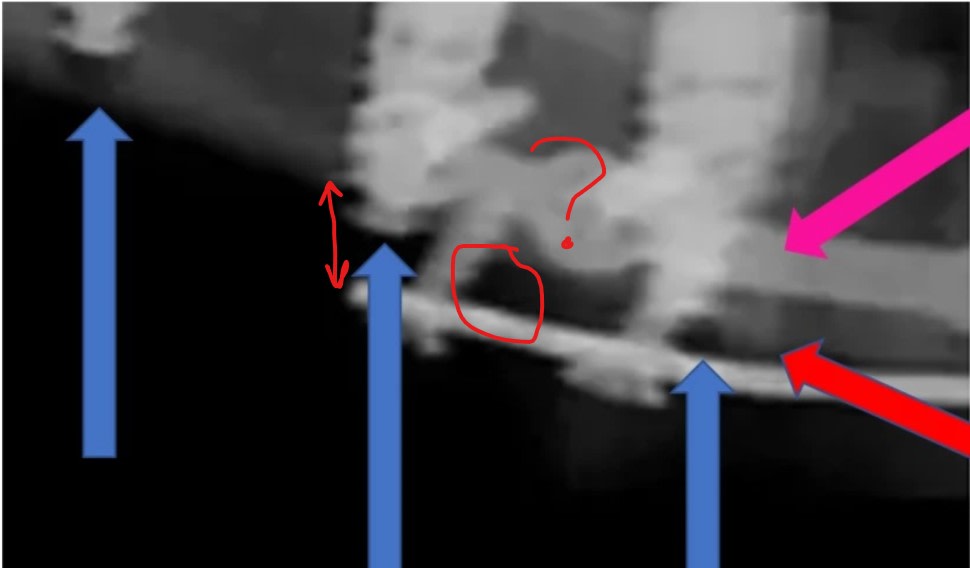

bin on le voit aussi l'espace au cbct, au milieu de ton cercle.

> bin on le voit aussi l'espace au cbct, au milieu de ton cercle.

A 1 an je vois une cratérisation sur le vis distale et de l'os entre la vis distale et celle en mésial alors que la pano laisse penser que la plaque d'ostéosynthèse est dans le vide. Ceci est la résultante de la position de la tangente de la portion d'ellipse lors de la prise panoramique.

on voit exactement la meme chose sur le pano et la cbct...

ouep... et l apex de l implant bien dans la corticale ;)

oui, regarde sa position sur la dernière photo et tu comprendras qu'il est contre la corticale et que la bande blanche que tu voie à la pano correspond au plat de l'os et la zone plus épaisse traversé par les rayons X.

canal du nerf dentaire inférieur

nerf dentaire inférieur